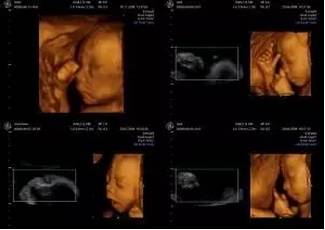

二、三维和四维超声

预约,so easy!!

三维和四维,只是坊间的通俗叫法,这“小名”与它的实际功能并无多大关系,它们的规范医学名称叫“胎儿系统筛查”(三维)、“胎儿系统筛查+面部成像”(四维)。

胎儿系统筛查(三维)基本每天都有空余名额

胎儿系统筛查+面部成像”(四维)只需于孕24周前预约即可

最佳检查时间为:

单胎,孕24周——28周

双胎,孕23周——25周

因双胎胎体相互遮挡,部分器官显示效果欠佳,故只限于“胎儿系统筛查”,不再做面部成像筛查。